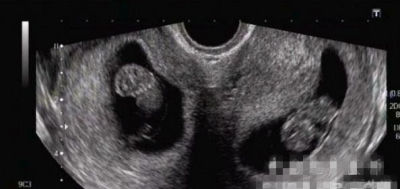

B超“透视”双子宫怀孕

摘要:双子宫是由于在发育过程中两侧副中肾管会合受阻所致的两个子宫各具一套输卵管、子宫、宫颈及阴道的异常现象,属于子宫发育异常的一种情况,故临床上双子宫是导致子宫性不孕的疾病之一。但双子宫怀孕在临床上也是比较常见的。

双子宫是双侧副中肾管未完全融合的结果,形成两个分离的宫体和宫颈,附有各自的输卵管、卵巢、圆韧带。双子宫、阴道纵隔、一侧阴道闭锁,常伴泌尿系统异常,多为一侧肾脏发育异常。